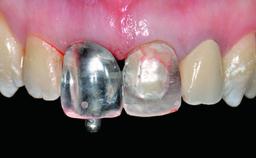

Replacement of a Failing Upper Left Central Incisor: Immediate Placement of an RC Bone Level Implant and Provisionalization

A healthy 23-year-old female patient was referred for a consultation on replacing tooth 21 with an implant-supported restoration. The patient had recently moved to the area and reported a history of endodontic and periodontal treatment for tooth 21. The tooth had been deemed non-restorable by her previous periodontist but since she was going to be moving, he recommended consulting to a dentist in her new city to continue her treatment. A review of her medical history yielded no significant findings and no known drug allergies. The analysis of her smile revealed a medium to high symmetrical smile line and a slightly discolored tooth 21.